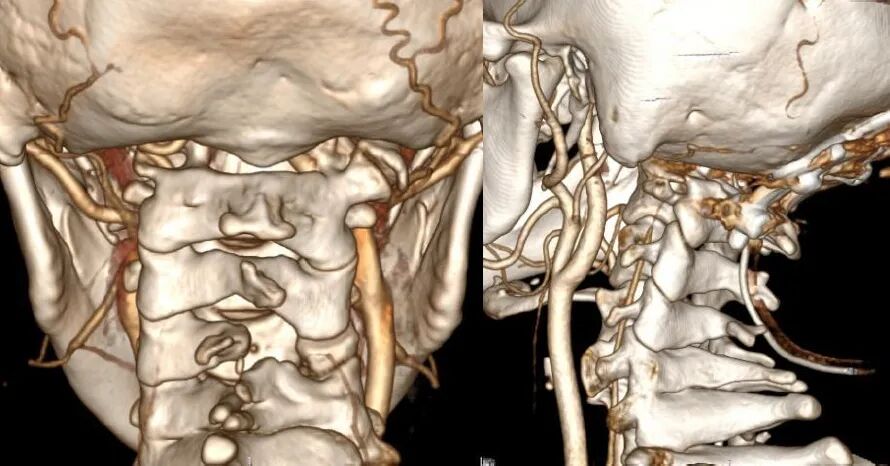

颅颈交界区骨性结构畸形常常伴有椎动脉走行异常,特别是寰枕融合畸形。当寰枕融合畸形发生时,寰椎后弓、两侧侧块、横突与枕骨融合消失,导致椎动脉V3段穿过枢椎横突孔后便失去了寰椎横突孔和寰椎后弓等骨性结构的引导,进而出现走行异常,椎动脉直接向内侧跨过枢椎椎弓峡部进入椎管。椎动脉V3段走行异常会遮挡寰枢椎关节面的后方(图8),增加了从后路在进行寰枢椎关节间操作和寰枢椎椎弓根置钉过程中损伤椎动脉的风险。

此外椎动脉的常见畸形还有椎动脉发育不良、甚至缺如。这导致优势椎动脉损伤后,发生致命性基底动脉缺血的风险增加,因此保护椎动脉是关节间撑开融合技术中的关键环节。

术前常规进行头颈部CTA扫描,应用计算机软件(推荐应用RadiAnt DICOM Viewer, Medixant Co.)对CTA Dicom数据进行三维重建详细观察颅颈交界区骨性结构畸形和椎动脉走行,制定手术方案,评估椎动脉损伤的风险。

根据进行关节间操作时损伤椎动脉的危险程度,将椎动脉走行分为3种类型:低风险型,高风险型,禁忌型低风险型椎动脉:椎动脉走行不遮挡寰枢椎关节面,进行关节间操作损伤椎动脉的风险较低,此类患者通常没有寰枕融合,或寰枕融合不完全,寰椎保留横突孔结构,椎动脉受到寰椎横突孔的引导,走行路径正常,没有遮挡寰枢椎关节面(图9)。

高风险型椎动脉:椎动脉走行遮挡寰枢椎关节面,在进行寰枢椎关节间撑开操作过程中,损伤椎动脉的风险较高。并进一步分为Ⅰ型、Ⅱ型和Ⅲ型危险型椎动脉。

Ⅰ型高风险型椎动脉指患者一侧椎动脉走行异常,手术中损伤几率较高,但对侧椎动脉走行、管径正常,手术中损伤几率较低。手术中高风险椎动脉发生损伤,对侧低风险椎动脉可以代偿基底动脉血运,患者发生后循环缺血的风险较低(图10)。

Ⅱ型高风险型椎动脉,指两侧椎动脉皆为高风险型椎动脉,由于两侧椎动脉均走行异常,因此术中均存在较高损伤风险,如两侧椎动脉同时被损伤,患者可能发生后循环缺血(图11)。

Ⅲ型高风险型椎动脉,指患者一侧椎动脉为高风险性椎动脉,而对侧椎动脉退化或缺如,一旦高风险型椎动脉损伤,对侧椎动脉无法代偿基底动脉血供,可引发致命性基底动脉缺血(图12)

对于高风险型椎动脉,我们采用的治疗策略是将椎动脉向头侧抬起。显露寰枢椎关节后缘后,将关节间撑开器完全插入关节,如此,在旋转撑开器对关节间隙进行撑开的过程中,与椎动脉接触的是撑开器柱状的连接杆,避免对椎动脉造成卡压和切割,降低椎动脉损伤的风险(图13)。

禁忌型椎动脉:椎动脉穿行于寰枢椎关节面,进行寰枢椎关节间操作必然损伤椎动脉(图14)。这种椎动脉走行方式在关节间操作过程中尚无有效办法避开,因此是关节间撑开操作的禁忌证。